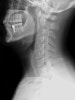

- 허리나 목이 아픈 환자가 X-ray를 찍고 나서 "일자목이라서 목이 아픈 거네요.", "일자허리라서 허리가 아픈 거네요."라는 말을 자주 듣게 됩니다.

일자목 또는 일자허리가 되는 것은 어떤 원인에 의한 결과이지 통증의 원인이 아닙니다.

일자목, 일자허리가 통증의 원인이 아니라 일자목, 일자허리를 만드는 원인이 통증의 원인입니다.

일자목이나 일자허리가 되는 주요 원인은 목이나 허리 근육의 긴장입니다.

일자목이나 일자허리가 진짜 통증의 원인이라면 치료방법은 목과 허리뼈의 정렬을 바로 잡는 것밖에 없을 것입니다.

하지만 기본적인 보존치료만으로도 목, 허리 통증은 많이 사라집니다.

통증 치료가 목적이라면 정렬을 바로 잡는 것보다는 먼저 목, 허리 근육의 이완이 선행되어야 할 것입니다.